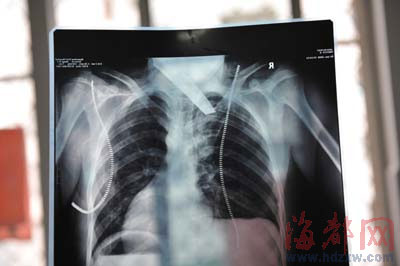

前晚,在第一醫(yī)院急救室,經(jīng)過(guò)4個(gè)多小時(shí)的搶救,醫(yī)生將匕首從小勇身上取出,發(fā)現(xiàn)這把匕首的刀尖扎斷了1厘米。由于小勇肺部被刺中,昨天上午,醫(yī)生再次進(jìn)行了3個(gè)多小時(shí)的手術(shù),切除了受傷的部分肺,直到下午,小勇才挺過(guò)來(lái)!巴α艘灰,現(xiàn)在總算醒了過(guò)來(lái)!睏钆恳灰箾](méi)睡,守在手術(shù)室外7個(gè)多小時(shí),生怕兒子再醒不過(guò)來(lái)。不過(guò),由于傷勢(shì)嚴(yán)重,小勇目前戴著氧氣呼吸,仍未脫險(xiǎn)。